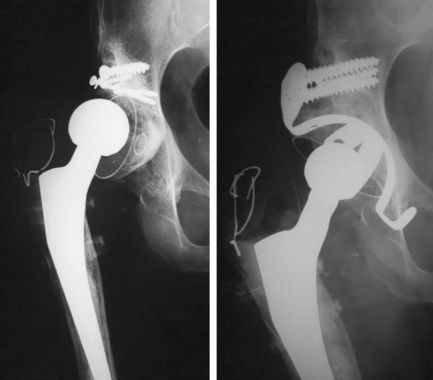

medical project total hip replacement